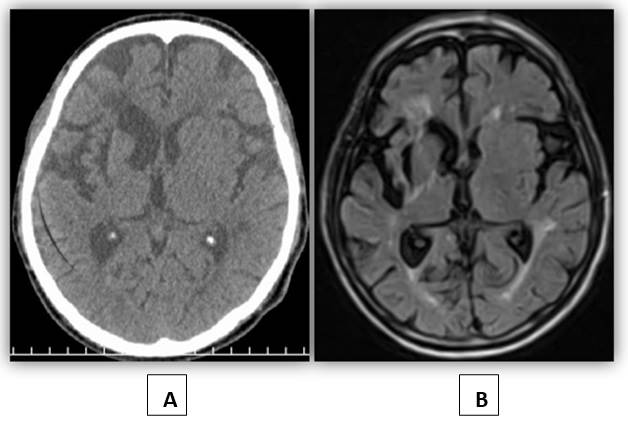

Tomografía axial computarizada (TAC) de cráneo: A nivel supratentorial en sustancia blanca periventricular derecha se evidencia hipodensidad de 10-13 UH de contornos irregulares que mide 48x18x36 mm, que produce atracción y ligera dilatación del ventrículo lateral ipsilateral en relación con lesión vascular antigua. Presenta otra hipodensidad a nivel pontino. Signos de atrofia cerebral difusa. (Figura 1).